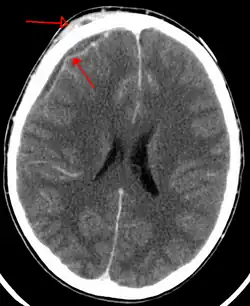

| An abscess that has led to an intracranial subdural empyema as seen on CT | |

Bacterial or occasionally fungal infection of the skull bones or air sinuses can spread to the subdural space, producing a subdural empyema. The underlying arachnoid and subarachnoid spaces are usually unaffected, but a large subdural empyema may produce a mass effect. Further, a thrombophlebitis may develop in the bridging veins that cross the subdural space, resulting in venous occlusion and infarction of the brain. With treatment, including surgical drainage, resolution of the empyema occurs from the dural side, and, if it is complete, a thickened dura may be the only residual finding. Symptoms include those referable to the source of the infection. In addition, most patients are febrile, with headache and neck stiffness, and, if untreated, may develop focal neurologic signs, lethargy, and coma. The CSF profile is similar to that seen in brain abscesses, because both are parameningeal infectious processes. If diagnosis and treatment are prompt, complete recovery is usual.